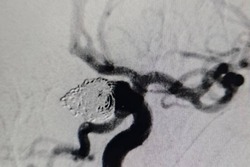

Астраханские врачи спасли пациентку с разрывом аневризмы

Благодаря современному ангиографу женщине успешно провели эндовазальную операцию, и уже через несколько дней она сможет вернуться к привычному образу жизни